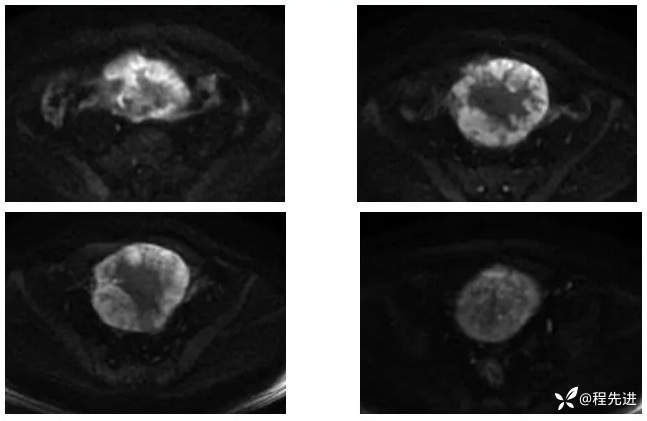

【腹盆】特别精彩病例|下腹痛20余天,男性病人腹腔巨大肿块该如何诊断

【患者信息】:男,41岁

【主诉】:下腹痛20余天

既往史:隐睾

肿瘤标志物:甲胎蛋白(AFP)>10000